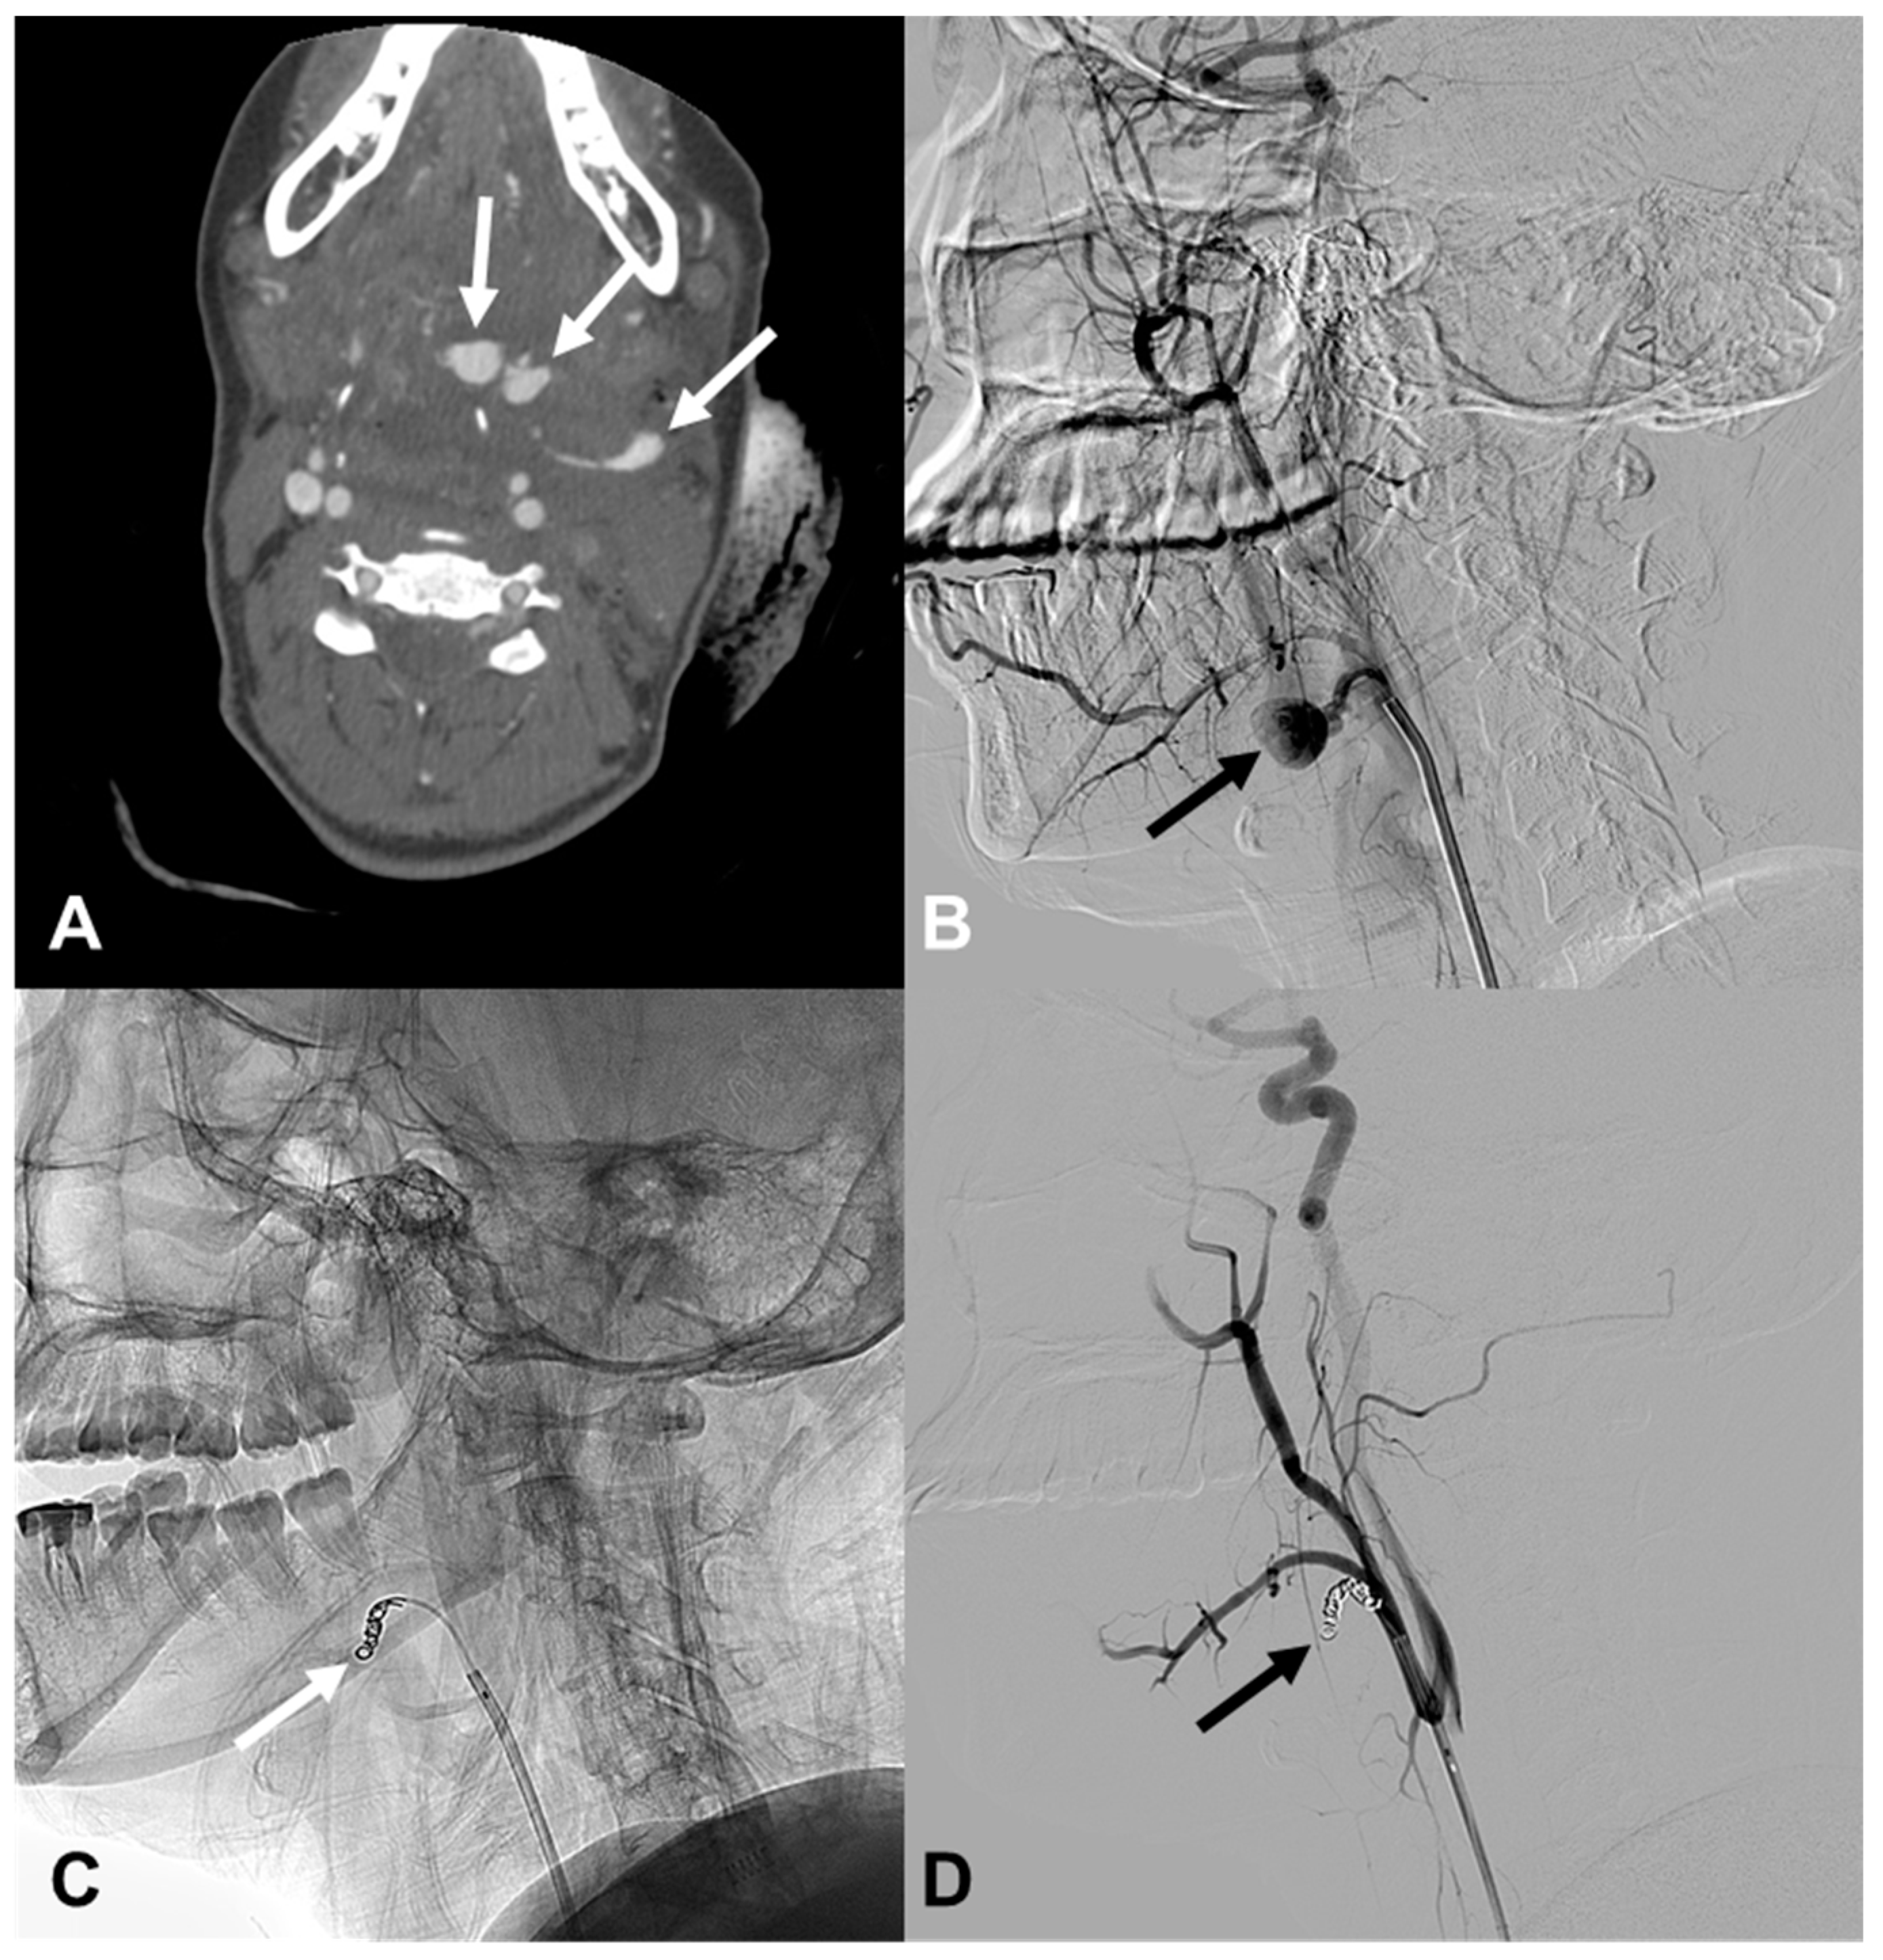

3.4. Carotid Artery Injury

| 5 | 39/M | Fall | Epistaxis | Facial and sphenoid bone fracture | EV, R IMA branch EV, R cavernous ICA (CCF) | Coil, particle | Stable 39 d F/U |

| 6 | 51/F | TA | Epistaxis and oral bleeding | Le fort I fracture | EV, R petrous ICA EV, R ascending pharyngeal | cStent, coil | Stable 423 d F/U |